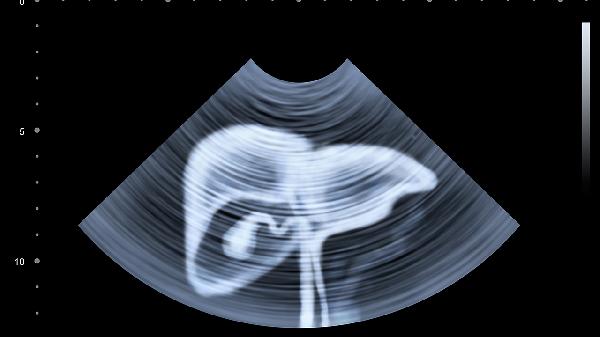

脂肪肝可能与肥胖、高脂饮食、胰岛素抵抗等因素有关,通常表现为肝区不适、转氨酶轻度升高、血脂异常等症状。超声检查可见肝脏回声增强,治疗可选用水飞蓟宾胶囊、多烯磷脂酰胆碱胶囊等护肝药物,配合有氧运动及低脂饮食。需定期监测肝功能及肝脏弹性检测。